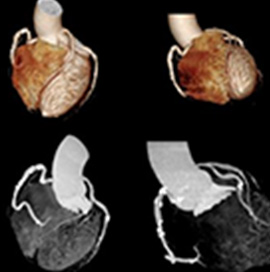

当院では心臓 CT・MRI 検査によって冠動脈を詳細に評価することができます。

「狭心症・心筋梗塞」は心臓の血管(冠動脈)が狭くなることで起こります。 当院では心臓 CT・MRI 検査によって冠動脈を詳細に評価することができます。